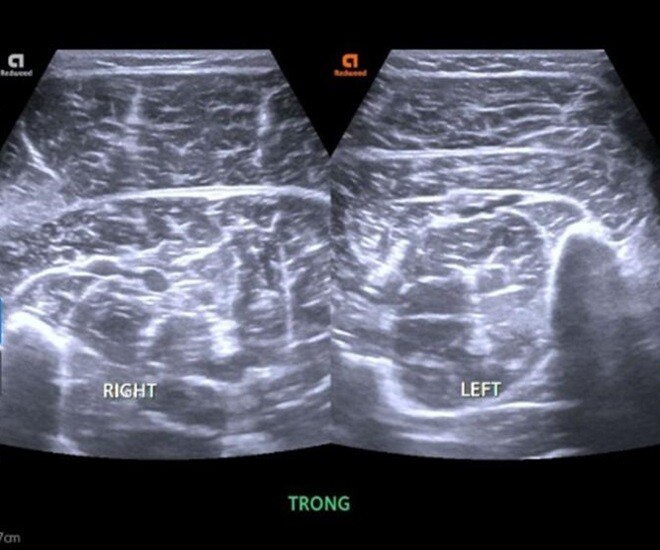

Sau khi thăm khám và làm các xét nghiệm, chụp chiếu cần thiết, N được xác định mắc cúm A. Trên hình ảnh siêu âm phần mềm chân phải phát hiện tình trạng phù nề cơ bụng chân trong - ngoài, cơ dép chân phải. Với kết quả trên, nam sinh được chẩn đoán xác định, bệnh nhân mắc cúm A có tổn thương tiêu cơ vân cấp. Ngay sau đó, bác sĩ đã đưa ra phác đồ kết hợp điều trị cúm A và tổn thương cơ. Đồng thời, bệnh nhân được hẹn tái khám định kỳ để đánh giá chức năng thận, kiểm tra các chỉ số men cơ như CK và điện giải đồ nhằm kịp thời phát hiện nguy cơ biến chứng.

Hình ảnh bất thường tại chân phải của nam sinh mắc cúm A được phát hiện trên hình ảnh siêu âm phần mềm. Ảnh: BSCC.